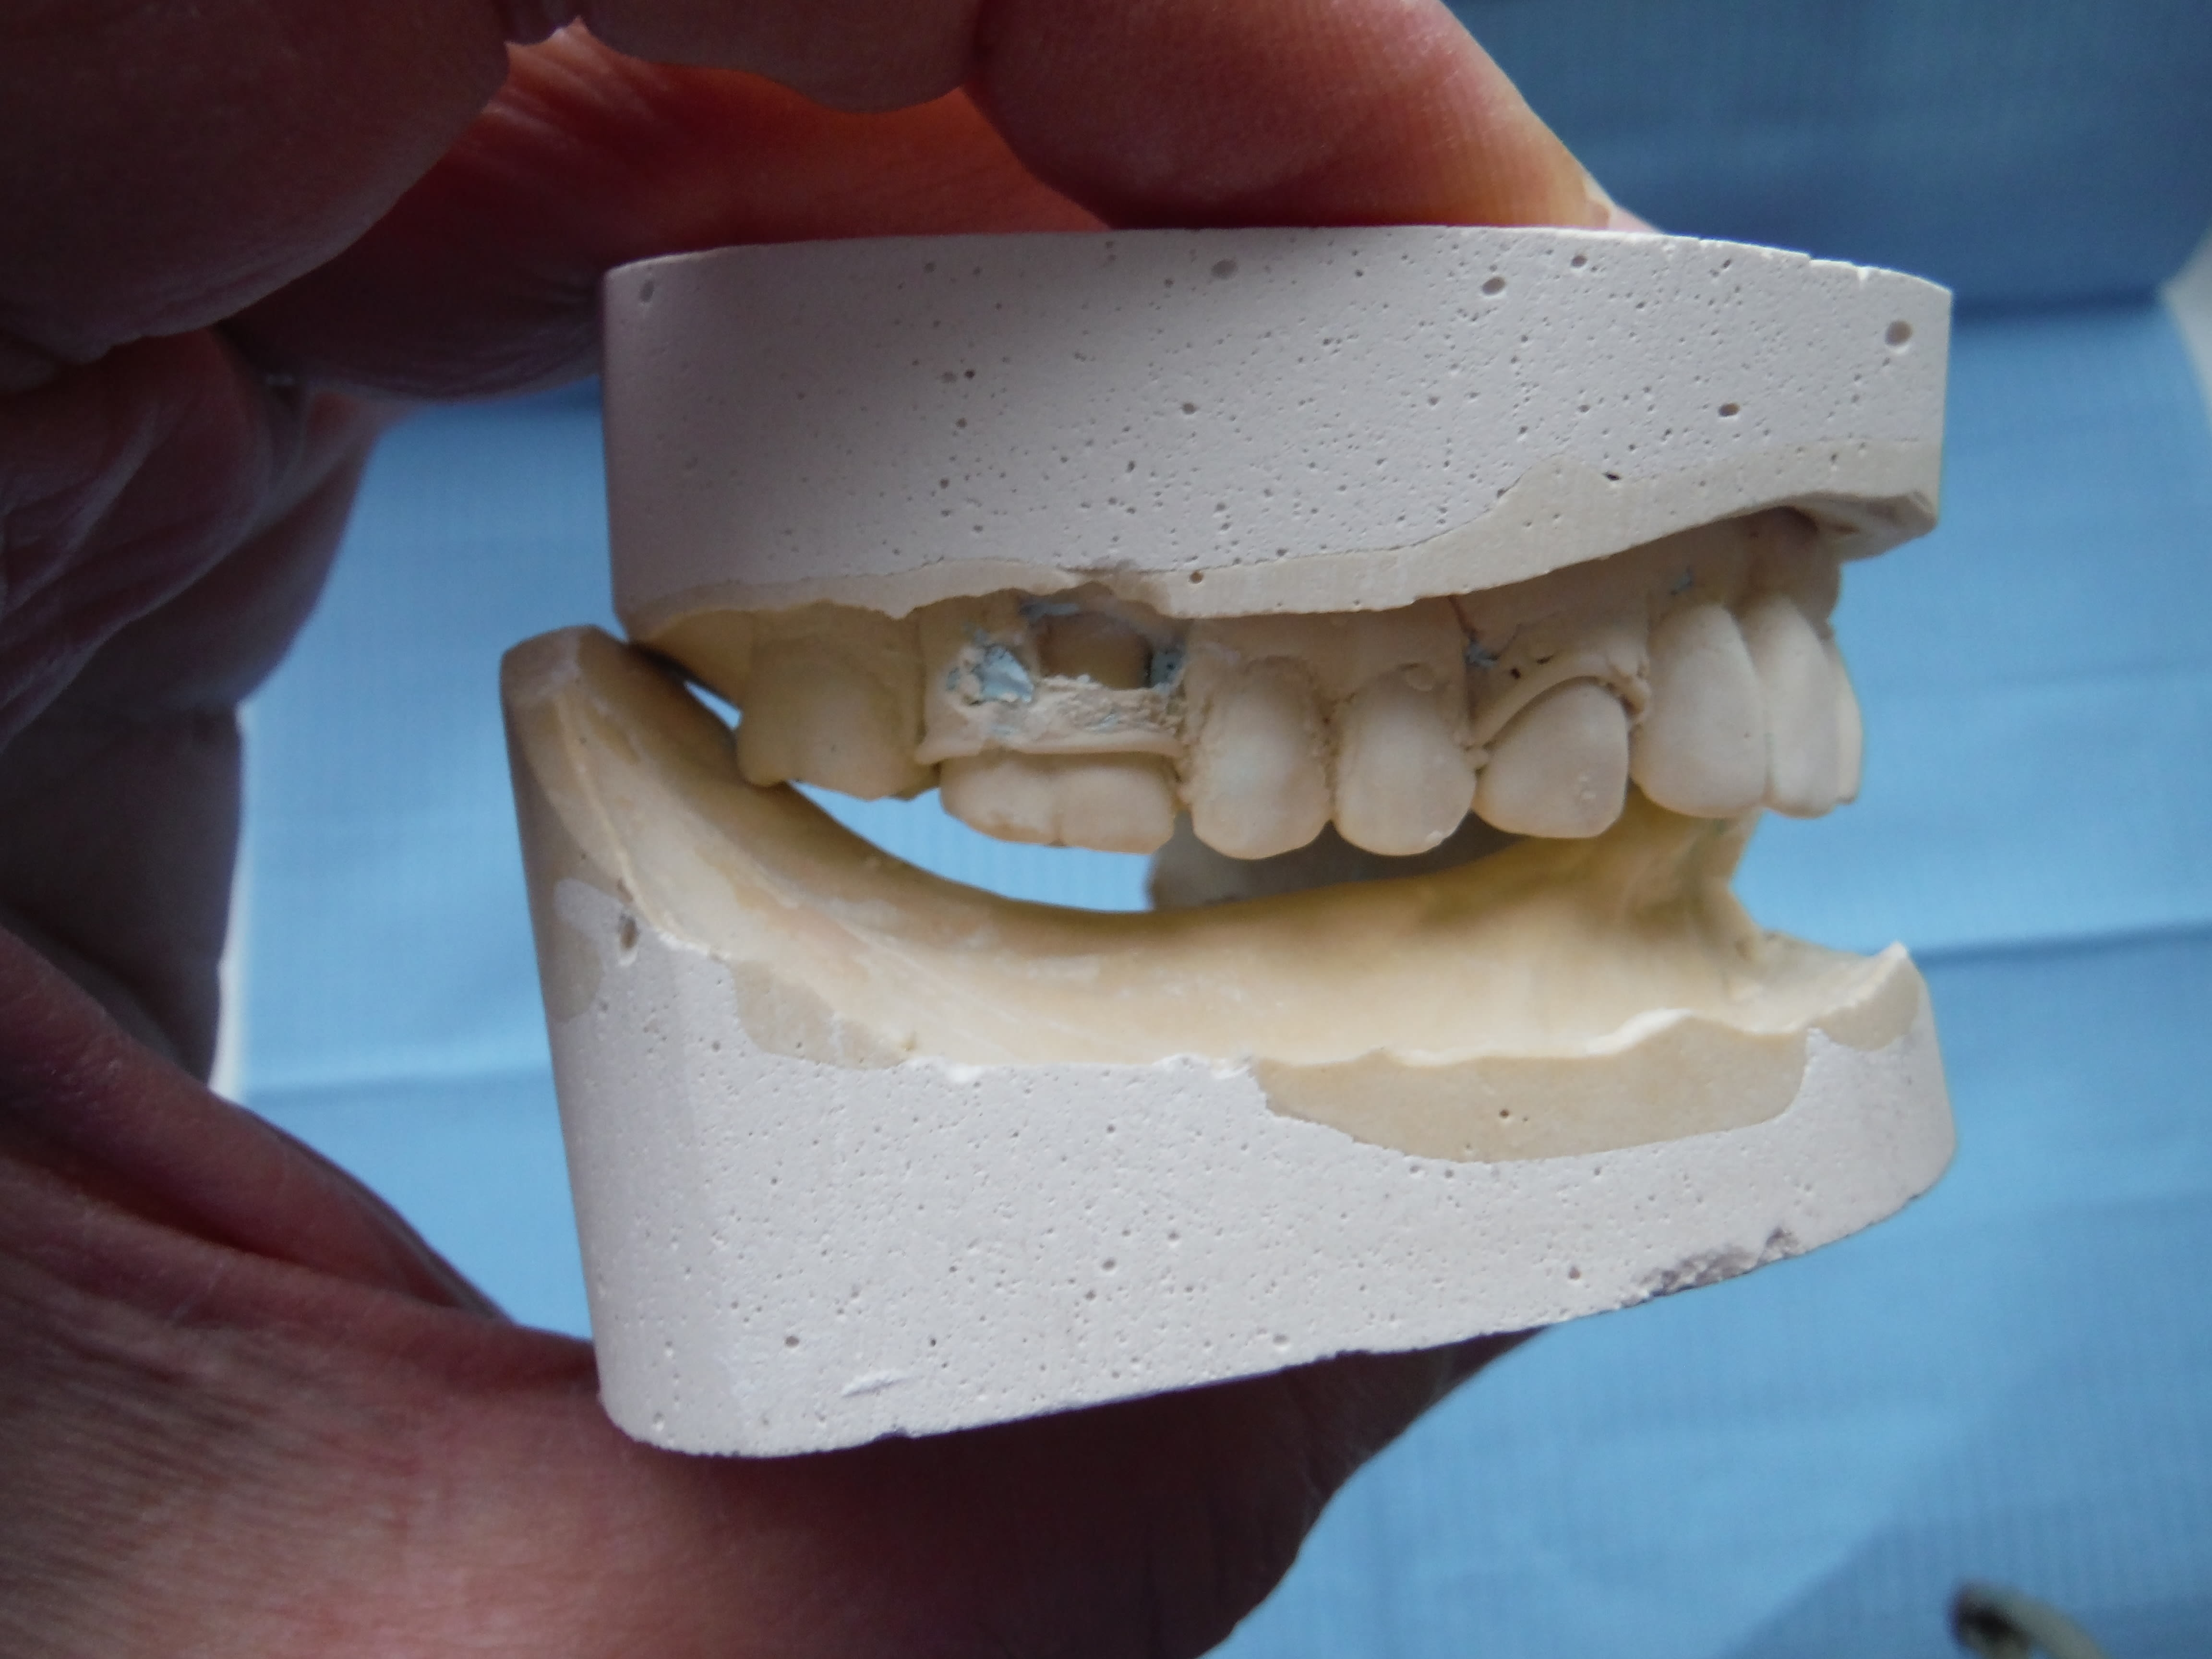

Et là tu vois quoi? Faut que j’adresse à un esssspécialiste?

Plus de 10 ans qu'il n'y a rien en bas, et là le coup de bol, elle s'est faite renverser par une voiture, avec les sous touchés elle va pouvoir se payer une pap/pac(?) C'est-y pas chouette?

La RC j't'en parle pas... trop simple!

Dscf3069 s3usgb - Eugenol

Dscf3070 saszen - Eugenol

Dscf3071 fpbucp - Eugenol

Je vois que tu vas en baver .:-)